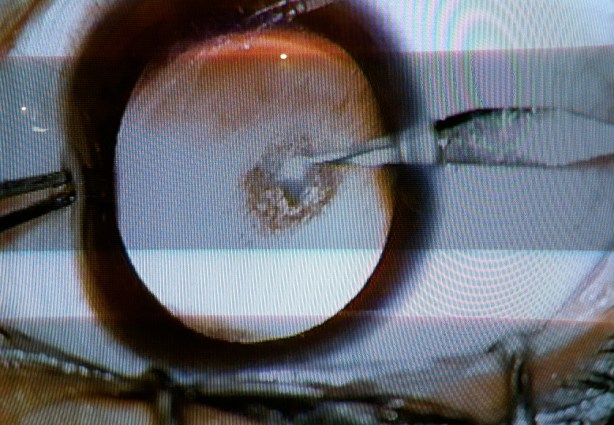

Nitish è sotto i ferri e io posso seguire l’operazione da vicino. Verrà operato prima all’occhio destro e tra un paio di giorni a quello sinistro. Il medico deve raschiare quel velo opaco che impedisce al bimbo di vedere, deve rimuovere il cristallino e inserirne uno nuovo sintetico. Su un monitor di fianco al lettino vedo le immagini dal microscopio. Ecco il momento in cui gli viene asportato il cristallino. Ha un bisturi infilato nell’occhio!

La benda viene tolta e subito un altro medico si avvicina. L’occhio viene pulito e Nitish rimane calmo. Non si sa ancora se riesce a vedere. C’è un silenzio surreale. Mi avvicino e faccio una foto… E parte il flash!!!!!!!!!!!! Noooooooooooooooo! Appena sbendati gli occhi sono estremamente fotosensibili e la luce forte provoca dolore. Con il cuore in gola per la tremenda cazzata chiedo subito al medico se posso aver compromesso l’operazione, ma lui scoppia a ridere vedendo la mia agitazione e mi rasserena. Non succederà niente. Tiro un sospiro di sollievo… Meno male! Ecco la foto in cui è partito il flash. C’è da dire che almeno così si vede bene la rifrazione della luce sul nuovo cristallino.